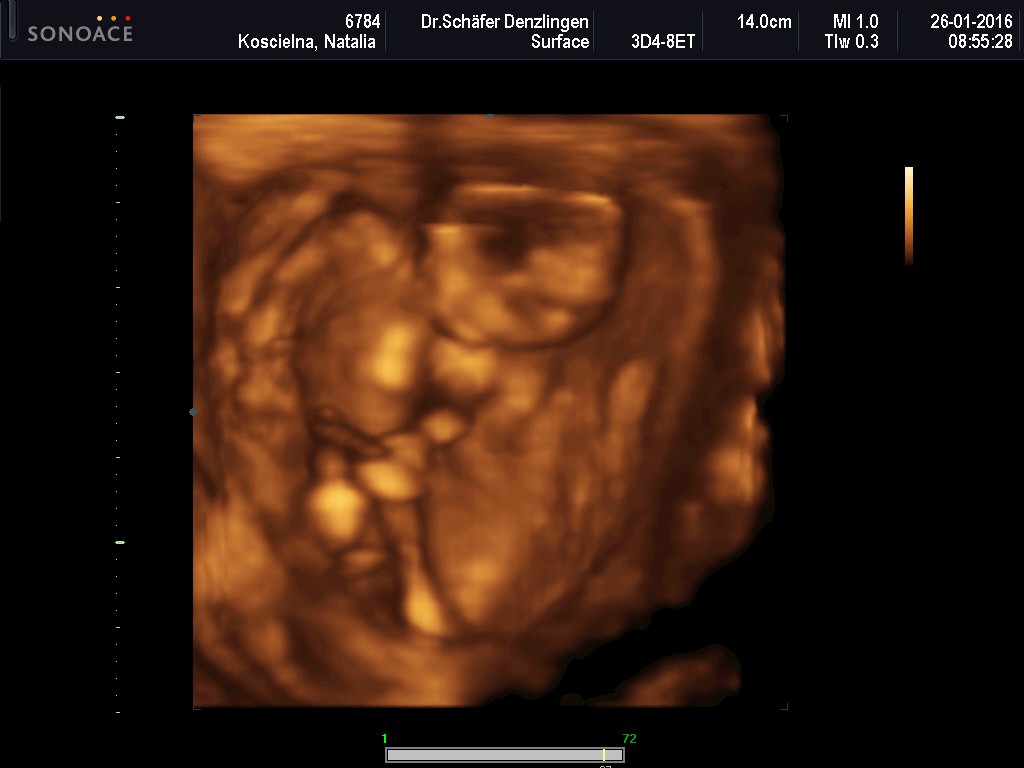

Wczoraj miałam wizytę - wszystko ok, ciąża troszkę większa, bo wszytskie pomiary pokazywały na 12+4, wszystko ok, więc ulga wielka, bardzo długo mi robił usg, mierzył i wszystko ok. Kolejne badania do zrobienia na tokspolazmoze a już sama chciałam sobie robić. Kolejna wizyta za 3 tygodnie. pokazuje zdjęcie z usg, po lewejrączka przy główce, na drugim nóżki i brzuszek![]()

dał mi zdjęcie i mówi :ma Pani swoje nóżki i rączki